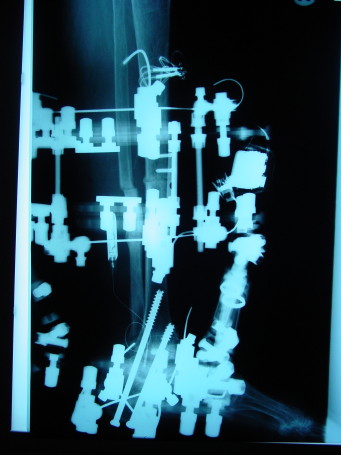

The first case involved a 63-year-old female who had a tibial-talar nonunion despite two previous attempts at treatment by another clinic. The patient subsequently developed a severe malposition secondary to progressive posterior tibial tendon dysfunction (PTTD). The correction entailed a tibial-calcaneal arthrodesis with intermetatarsal nail, external fixation and implantable direct current bone stimulation. She achieved good consolidation at just eight weeks postoperatively.

The third case involves a 60-year-old patient with rheumatoid arthritis and a tibial varum deformity. The center of rotation of angulation (CORA) was midshaft. Accordingly, this was a high risk bone healing site. The patient underwent corrective tibial osteotomy and a tibio-talar-calcaneal arthrodesis.

After we performed a proximal tibial osteotomy, we had the patient wear a capacitive coupling bone stimulation device 24 hours a day for 12 weeks. We utilized a direct current implantable device at the distal ankle. The patient achieved good union at 16 weeks postoperatively.